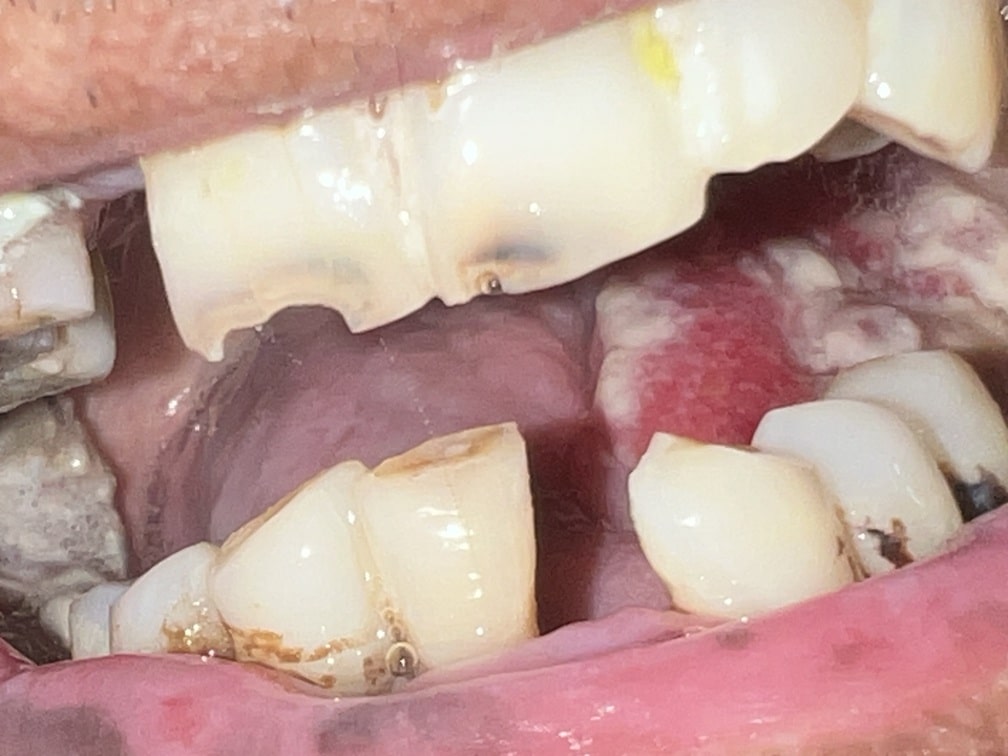

42 years old male suffering from right lower Gingivo buccal growth involving mandible .CT scan shows level 1 ,2 lymphadenopathy .Right modified neck dissection with right hemimandibulectomy with right pectoralis flape done.

21-04-2026